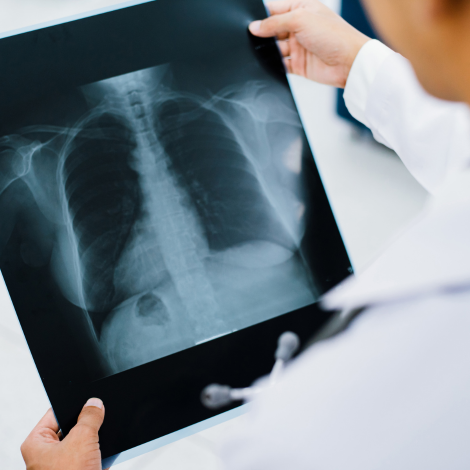

Chest X-ray

If you have symptoms such as feeling short of breath, a chest X-ray can help doctors find out if it’s caused by a heart or lung condition or something else. You would also have a chest X-ray done as part of routine health-check, pre-employment check or work up for any surgery.